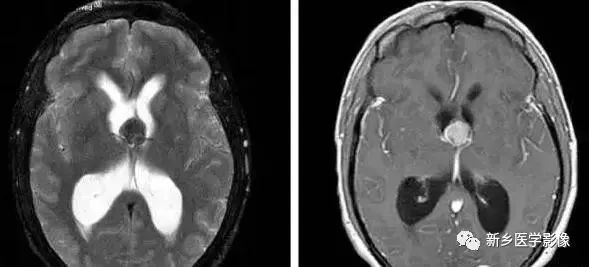

1.导水管狭窄:

中脑导水管是脑室系统最狭窄的通道,也是脑脊液循环受阻最常见的部位。

导水管狭窄的病因比较复杂、主要包括:①先天发育性狭窄②导水管周围胶样变③导水管粘连等。先天发育性狭窄可呈线样狭窄、分叉样狭窄或横膈膜形成。导水管周围胶样变多为炎症所致,主要见于宫内先天感染后,尤其是弓形体感染。

导水管粘连主要见一于颅内感染和出血后,可于胚胎期发生,也可见于出生后任何年龄。导水管粘连所致狭窄多位于导水管远端。 狭窄段长度通常为2一5mm,狭窄近端异水管可呈喇叭口样扩张。

导水管狭窄时,三脑室扩大常很显著,三脑室前部视隐窝和漏斗隐窝扩张或消失,三脑室后部松果体隐窝和松果体上隐窝明显后突,向小脑上池疝入。严重者可压迫小脑。